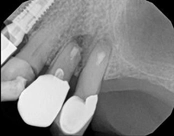

Apicoectomies, including molar apicoectomies:

Before

After

3-month follow-upThis person saw a specialist and was told the molar tooth needed to be extracted because the root canal failed and was infected. The root canal had been done by an endodontic specialist. The diagnosis was: previous endodontic treatment, chronic periradicular abscess. We did an apicoectomy and saved the patient’s tooth.